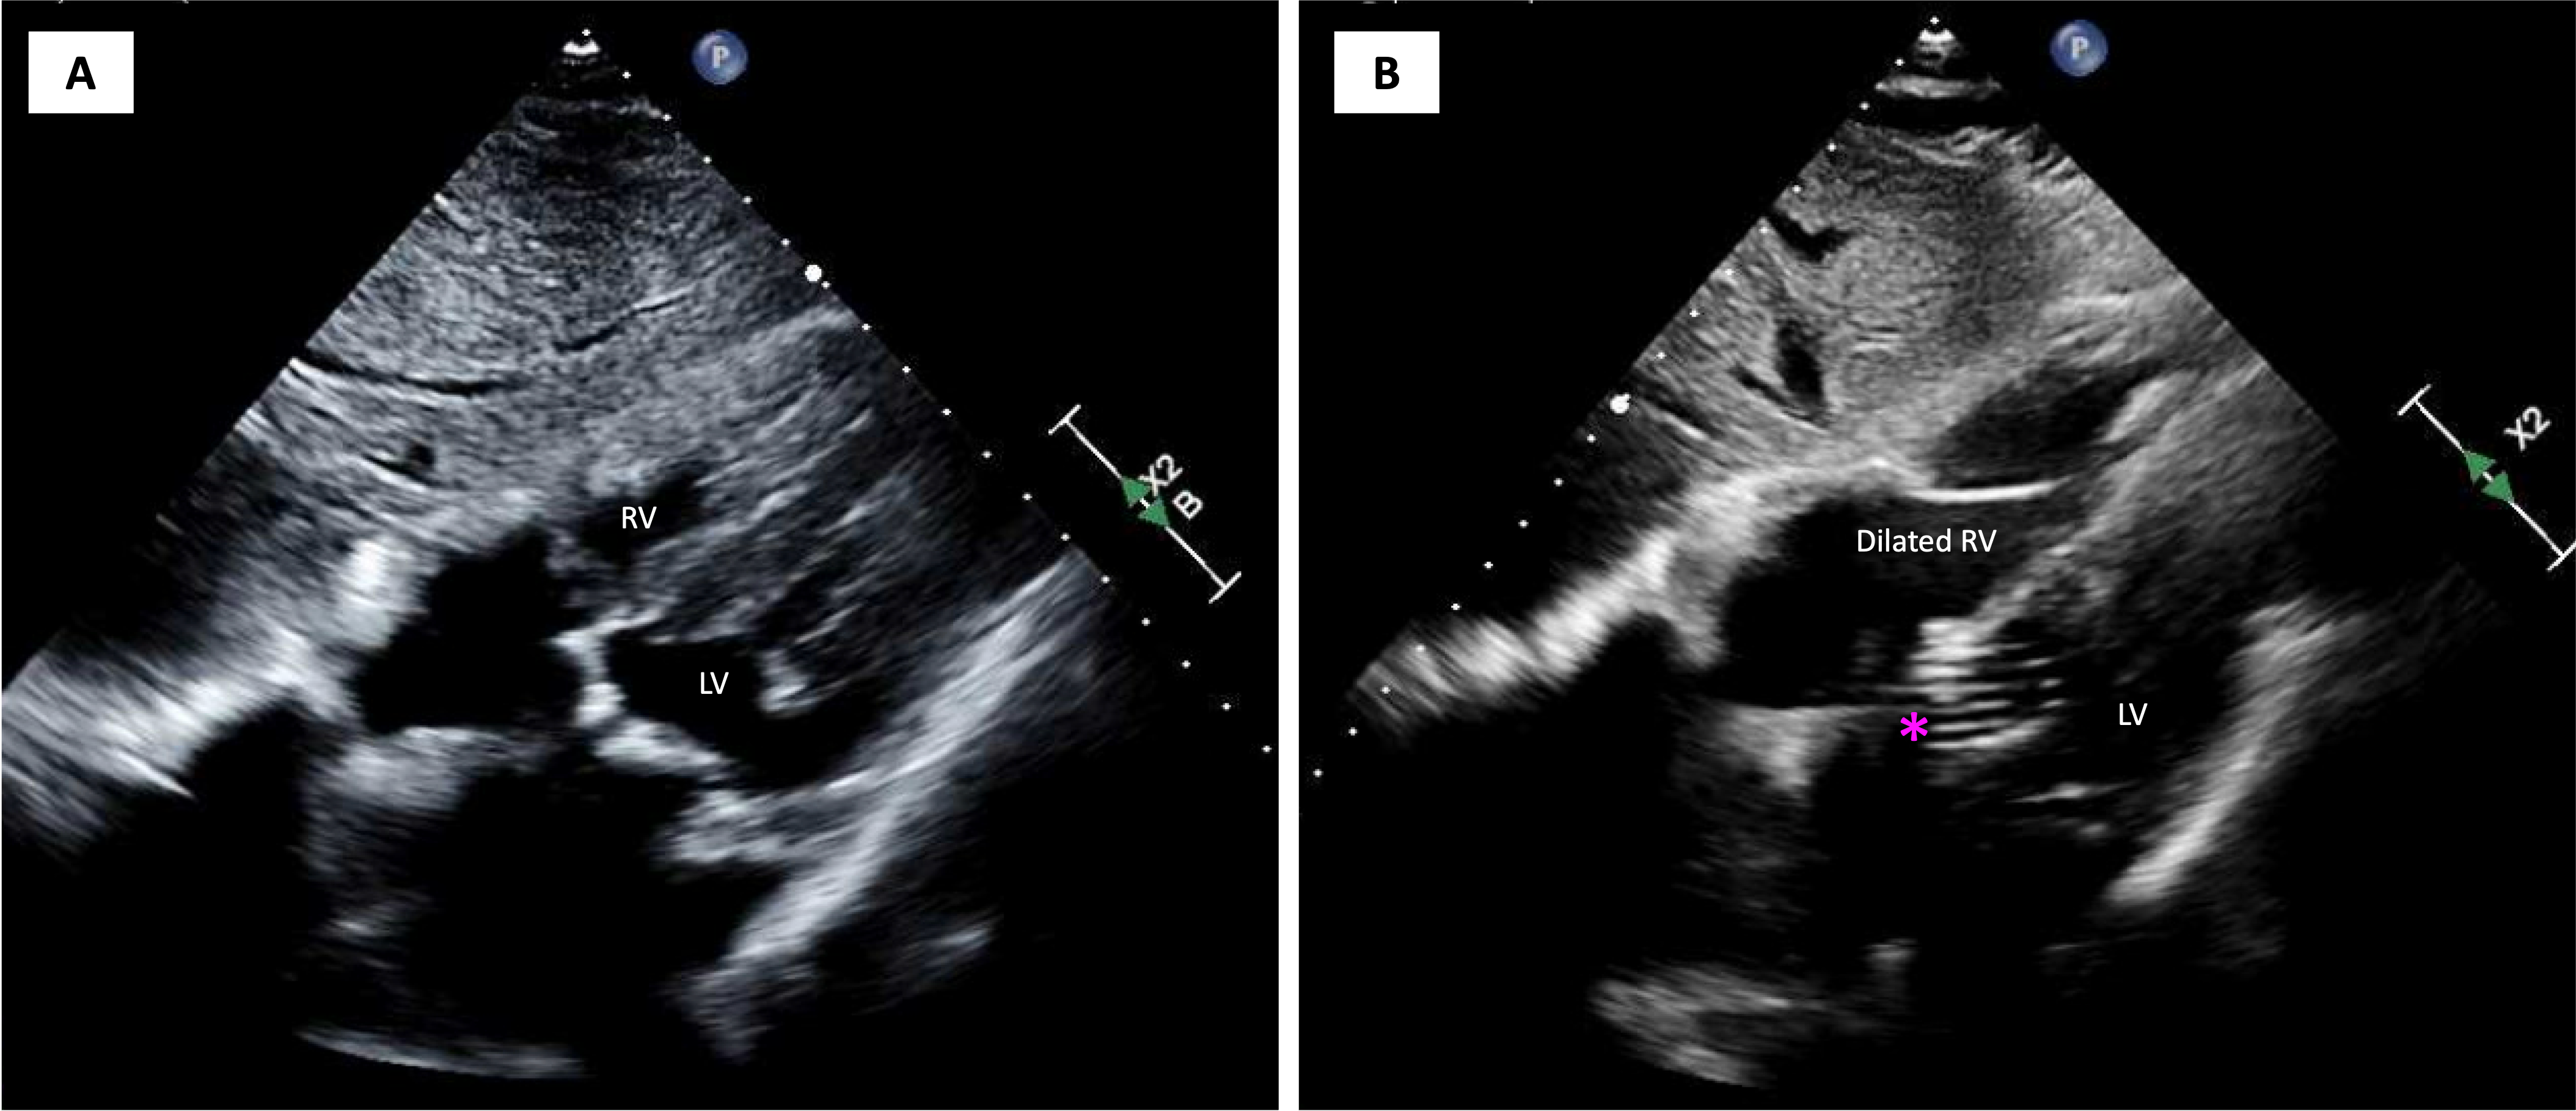

A 93-year-old woman with symptomatic severe aortic stenosis and normal biventricular function was referred for transcatheter aortic valve replacement (TAVR) evaluation (Figure 1A, Video 1). Cardiac computed tomography revealed safe coronary heights and multiple large calcified mobile mass-like structures attached to the aortic valve (AV), confirmed also by transesophageal echocardiography, which were thought to be prominent Lambl’s excrescences. (Figure 2, Videos 2 and 3). Coronary angiography found a 50% to 60% calcified lesion in the proximal right coronary artery (RCA) (Figure 3A, Video 4). Aortic arch vessels were deemed not suitable for cerebral embolic protection.

Transfemoral TAVR with 26-mm Evolut FX valve (Medtronic) was successfully performed. Commissural misalignment was noted (Figure 4). The implant depth was 4 mm and RCA flow was present (Video 5). Transthoracic echocardiography (TTE) showed no paravalvular regurgitation, a mean gradient of 3 mm Hg, and normal biventricular function (Video 6). The patient was pacing-dependent after valve deployment. Two hours afterwards, the patient became hypotensive and developed polymorphic ventricular tachycardia requiring electrical cardioversion. TTE revealed right ventricular dilation and severe dysfunction (Figure 1B, Video 7). An intra-aortic balloon pump was placed and repeat coronary angiography found a total occlusion of the RCA ostium (Figure 3B, Video 8), which was successfully treated by percutaneous coronary intervention with 2 drug-eluting stents (Figure 3C, Video 9). The patient clinically improved and was safely discharged home on post-op day 10.